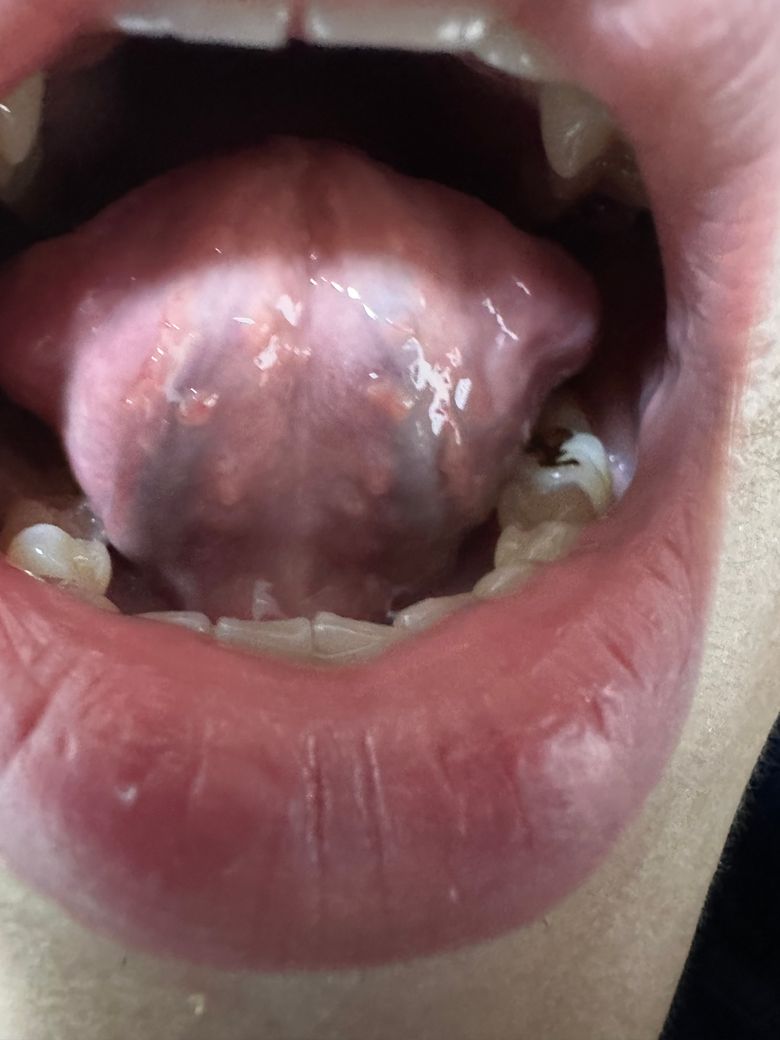

구강 hpv 혀 밑에 돌기들 있는데 맞나요? 후두hpv 인가요? 이빈후과에서 인후염 이라는데 3개월정도 지속 됩니다 hpv 인가요?

구강hpv 혀 밑에 돌기들 있는데 맞나요? 아 그리고 목 인후염이 3개월 정도 가나요? 인후염 후두에 hpv 생기나요? 인후 쫌에 하나염증 하나랑 빨강여즘 여러게 있습니다 또 이빈후과에서 인후염 이라는데

이상해서 올립니다 입안 목에 흰염증 빨강염증 양 옆에 염증들 이 3개월 지속 입니다 목 따가움 가끔 있고 말 많이하면 허스키한 목소리 나옵니다 자세한 답변 해주시면 감사하겠습니다

• 1번 째 사진

이비인후과 진료와 검사를 이미 받아보셨고 그곳에서 인후염이라고 했다면 우선 진단을 빋고 처방 받으신대로 약을 드셔보시는게 맞는 듯 합니다. 후두 유두종을 걱정하고 계신데 사진상으로 보면 진단에 맞는 전형적인 병변은 아닙니다. 이 진단을 백프로 배제하고 싶으시다면 다시 이비인후과 진료 및 검사 받아보셔야 될듯합니다. 감사합니다